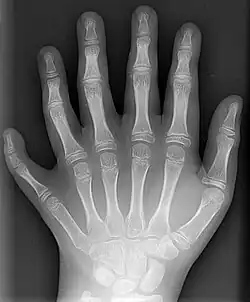

Mit Röntgenstrahlung kann der menschliche Körper durchleuchtet werden, wobei vor allem Knochen, aber bei modernen Geräten auch innere Organe sichtbar werden (siehe auch Röntgen). Dabei wird ausgenutzt, dass das in den Knochen vorkommende Element Calcium mit Z = 20 eine deutlich höhere Ordnungszahl hat als die Elemente, aus denen die weichen Gewebe hauptsächlich bestehen, nämlich Wasserstoff (Z = 1), Kohlenstoff (Z = 6), Stickstoff (Z = 7) und Sauerstoff (Z = 8). Zudem werden Röntgenkontrastmittel eingesetzt, die meist Iod (Z = 53) oder Barium (Z = 56) enthalten. Neben herkömmlichen Geräten, die eine zweidimensionale Projektion produzieren, werden auch Computertomographen eingesetzt, die eine räumliche Rekonstruktion des Körperinneren ermöglichen.